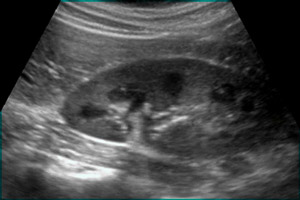

Ультразвуковая диагностика является основным методом обследования почек. С помощью ультразвука можно определить форму, размеры, структуру и толщину стенок почек, а также их расположение и взаимодействие с соседними органами. Ультразвуковая эхография также позволяет оценить состояние паренхимы почек и чашечно-лоханочного аппарата, обнаружить наличие камней, опухолей и смещение органов. Допплерография, или ультразвуковое исследование сосудов, помогает оценить состояние вен и артерий почек и выявить повреждения. Существуют различные виды допплер-сканирования, включая цветное, тканевое и энергетическое, которые применяются для разных целей. Ультразвуковая диагностика почек доступна для всех и может быть проведена по рекомендации врача или по собственному желанию.

Врач-сонолог проводит интерпретацию результатов и в заключении указывает информацию о количестве почек, их расположении, форме и размере, а также о подвижности. Также описывается состояние мочеточников, структура паренхимы и чашечно-лоханочного аппарата. Для лучшего понимания расшифровки УЗИ почек полезно знать следующую информацию: если орган здоров, то его контуры четкие; почечная лоханка – это полость, в которой собирается урина из чашечек; затемнение на снимке может указывать на наличие песка или микрокалькулеза; эхогенное образование может быть камнем в почке, размеры которого минимально составляют 4-5 мм. Пациенту выдается бланк с результатами и описанием, а также снимки УЗИ, на которых указываются стрелочками обнаруженные патологии. Эти снимки служат подсказкой для лечащего врача при постановке диагноза.